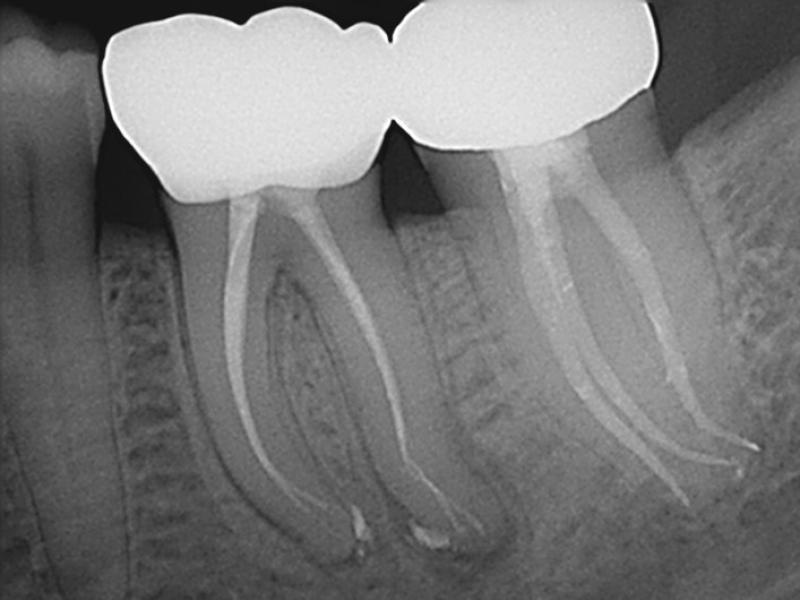

Pre-Op